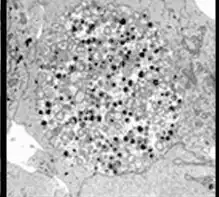

Chlamydia pneumoniae in HeLa cell 72 hours post infection

Chlamydia pneumoniae has a complex life cycle and must infect another cell to reproduce; thus, it is classified as an obligate intracellular pathogen. The full genome sequence for C. pneumoniae was published in 1999.[6] It also infects and causes disease in koalas, emerald tree boas (Corallus caninus), iguanas, chameleons, frogs, and turtles.